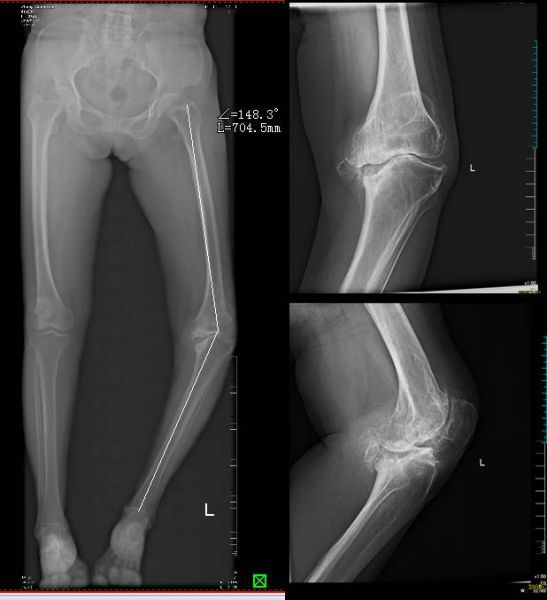

71岁的张某,约8年前出现左膝疼痛,2年前疼痛愈发严重,无法正常行走,苦不堪言,严重影响生活质量。张某及家人曾于多家医院就诊。由于张某左膝长期处于半脱位状态导致外侧韧带松弛,内侧韧带挛缩,术中平衡两侧韧带是巨大挑战,胫骨内侧平台严重塌陷骨缺损,常规人工关节材料不能修复骨缺损,手术难度大,风险高,预后差。多方打听后,家人慕名来到州人民医院骨一科找到赵峻主任,赵峻详细检诊后认为患者左膝重度骨性关节炎、左膝内翻畸形、僵直膝诊断明确,膝关节置换手术是最佳治疗方案。

术前X片